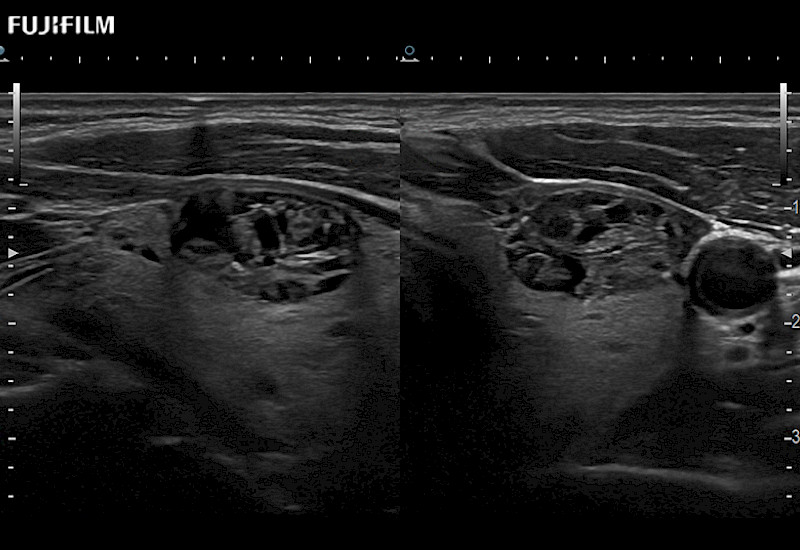

for use during open and laparoscopic procedures: Tumor localization & staging, Ablation, Resection, Biopsy, Transplant, Abdominal exploration, Robotic surgery

Our dedication to Surgical Oncology allows us to offer superior image quality, outstanding system reliability and intuitive use of cutting edge technology.

The ARIETTA 750 incorporates all of the proven technologies and functions that medical professionals have come to expect from Fujifilm Healthcare.

ARIETTA 750 is the definitive diagnostic ultrasound solution for any clinical setting - Private Office, Imaging Center, or Hospital. The ARIETTA platform provides the ultimate in clinical performance with its state-of-the-art features and large user-friendly display.

The ARIETTA 650 DI combines trusted Fujifilm Healthcare technologies and features tailored for surgical oncology.

Designed to meet the demands of surgeons, the ARIETTA 650 DI offers precise guidance. Its advanced capabilities and large, intuitive display offer accurate and efficient care in operating rooms and specialized surgical settings.